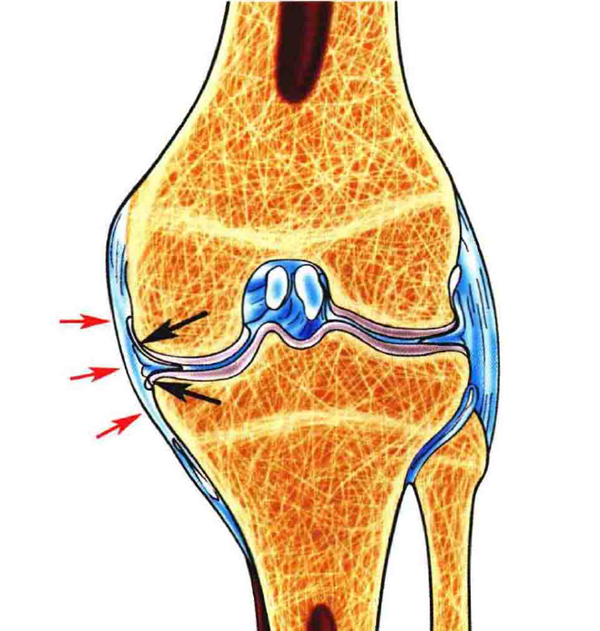

膝关节内侧副韧带(MCL)损伤是膝关节最常见的损伤之一,绝大多数MCL损伤不需要手术治疗,内侧副韧带浅层(sMCL)、后内侧关节囊(PMC)、后斜韧带(POL)对维持膝关节外翻和旋转稳定发挥着不同的作用。直接的外翻应力伴有胫骨外旋是导致MCL损伤的最主要因素。

图 1黑色箭头为内侧副韧带深层,红色剪头为内侧副韧带浅层